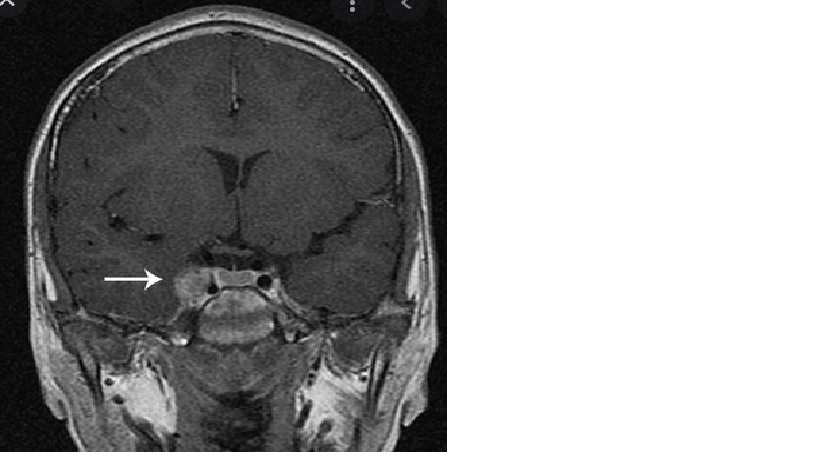

BN được chụp MRI xoang hang

MRI T1W sau cản quang, coronal (left) và sagittal (right, scaled down). Lưu ý sự tăng cường đồng nhất của khối u chiếm và nhô ra qua thành bên của xoang hang trái. Đầu mũi tên màu vàng cho thấy một phần nhỏ ngoài hang. Động mạch cảnh trong bị hẹp và di lệch được bao bọc (mũi tên trắng). Tuyến yên bị đẩy sang phải (dấu sao vàng).